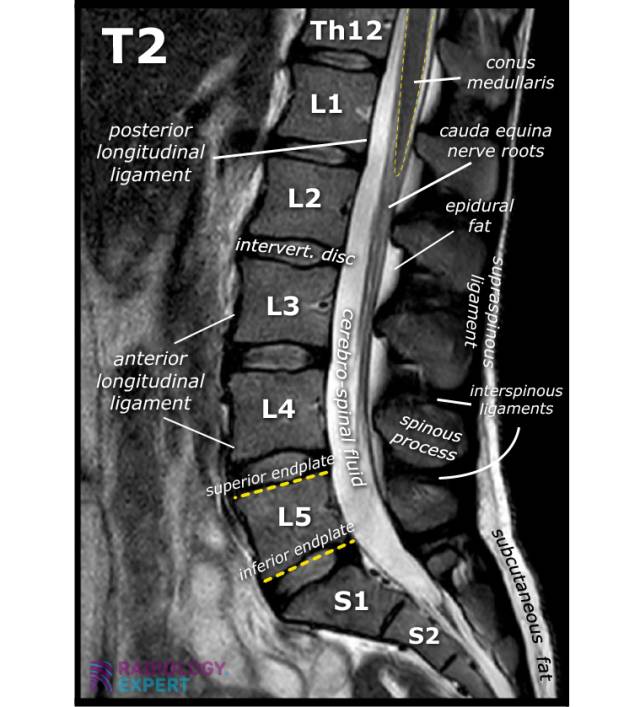

Anatomy MRI lumbar spine Anatomy MRI lumbar spine

Click image to see overlay